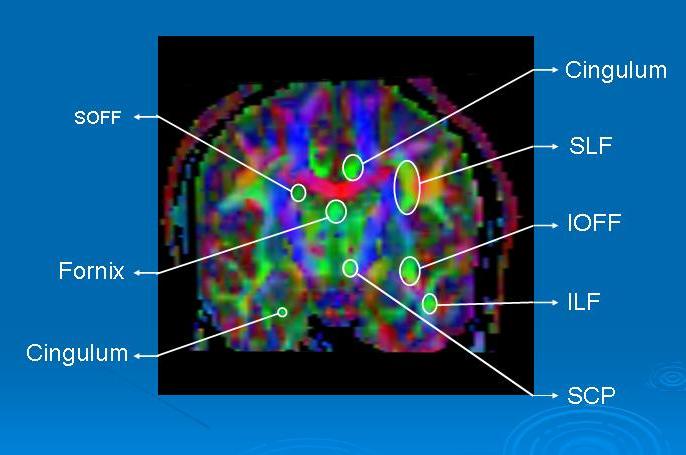

Coronal view (figure 2) is better to show the fibers oriented posteior-anterior or anterior-posterior, coded in green.

Figure 2. Coronal FA Map.

- SOFF: Superior Occipito-frontal Fasciculus

- SLF: Superior Longitudinal Fasciculus

- IOFF: Inferior Occipito-frontal fasciculus

- ILF: Inferior Longitudinal Fasciculus.

- SCP: Superior Cerebellar Peduncle